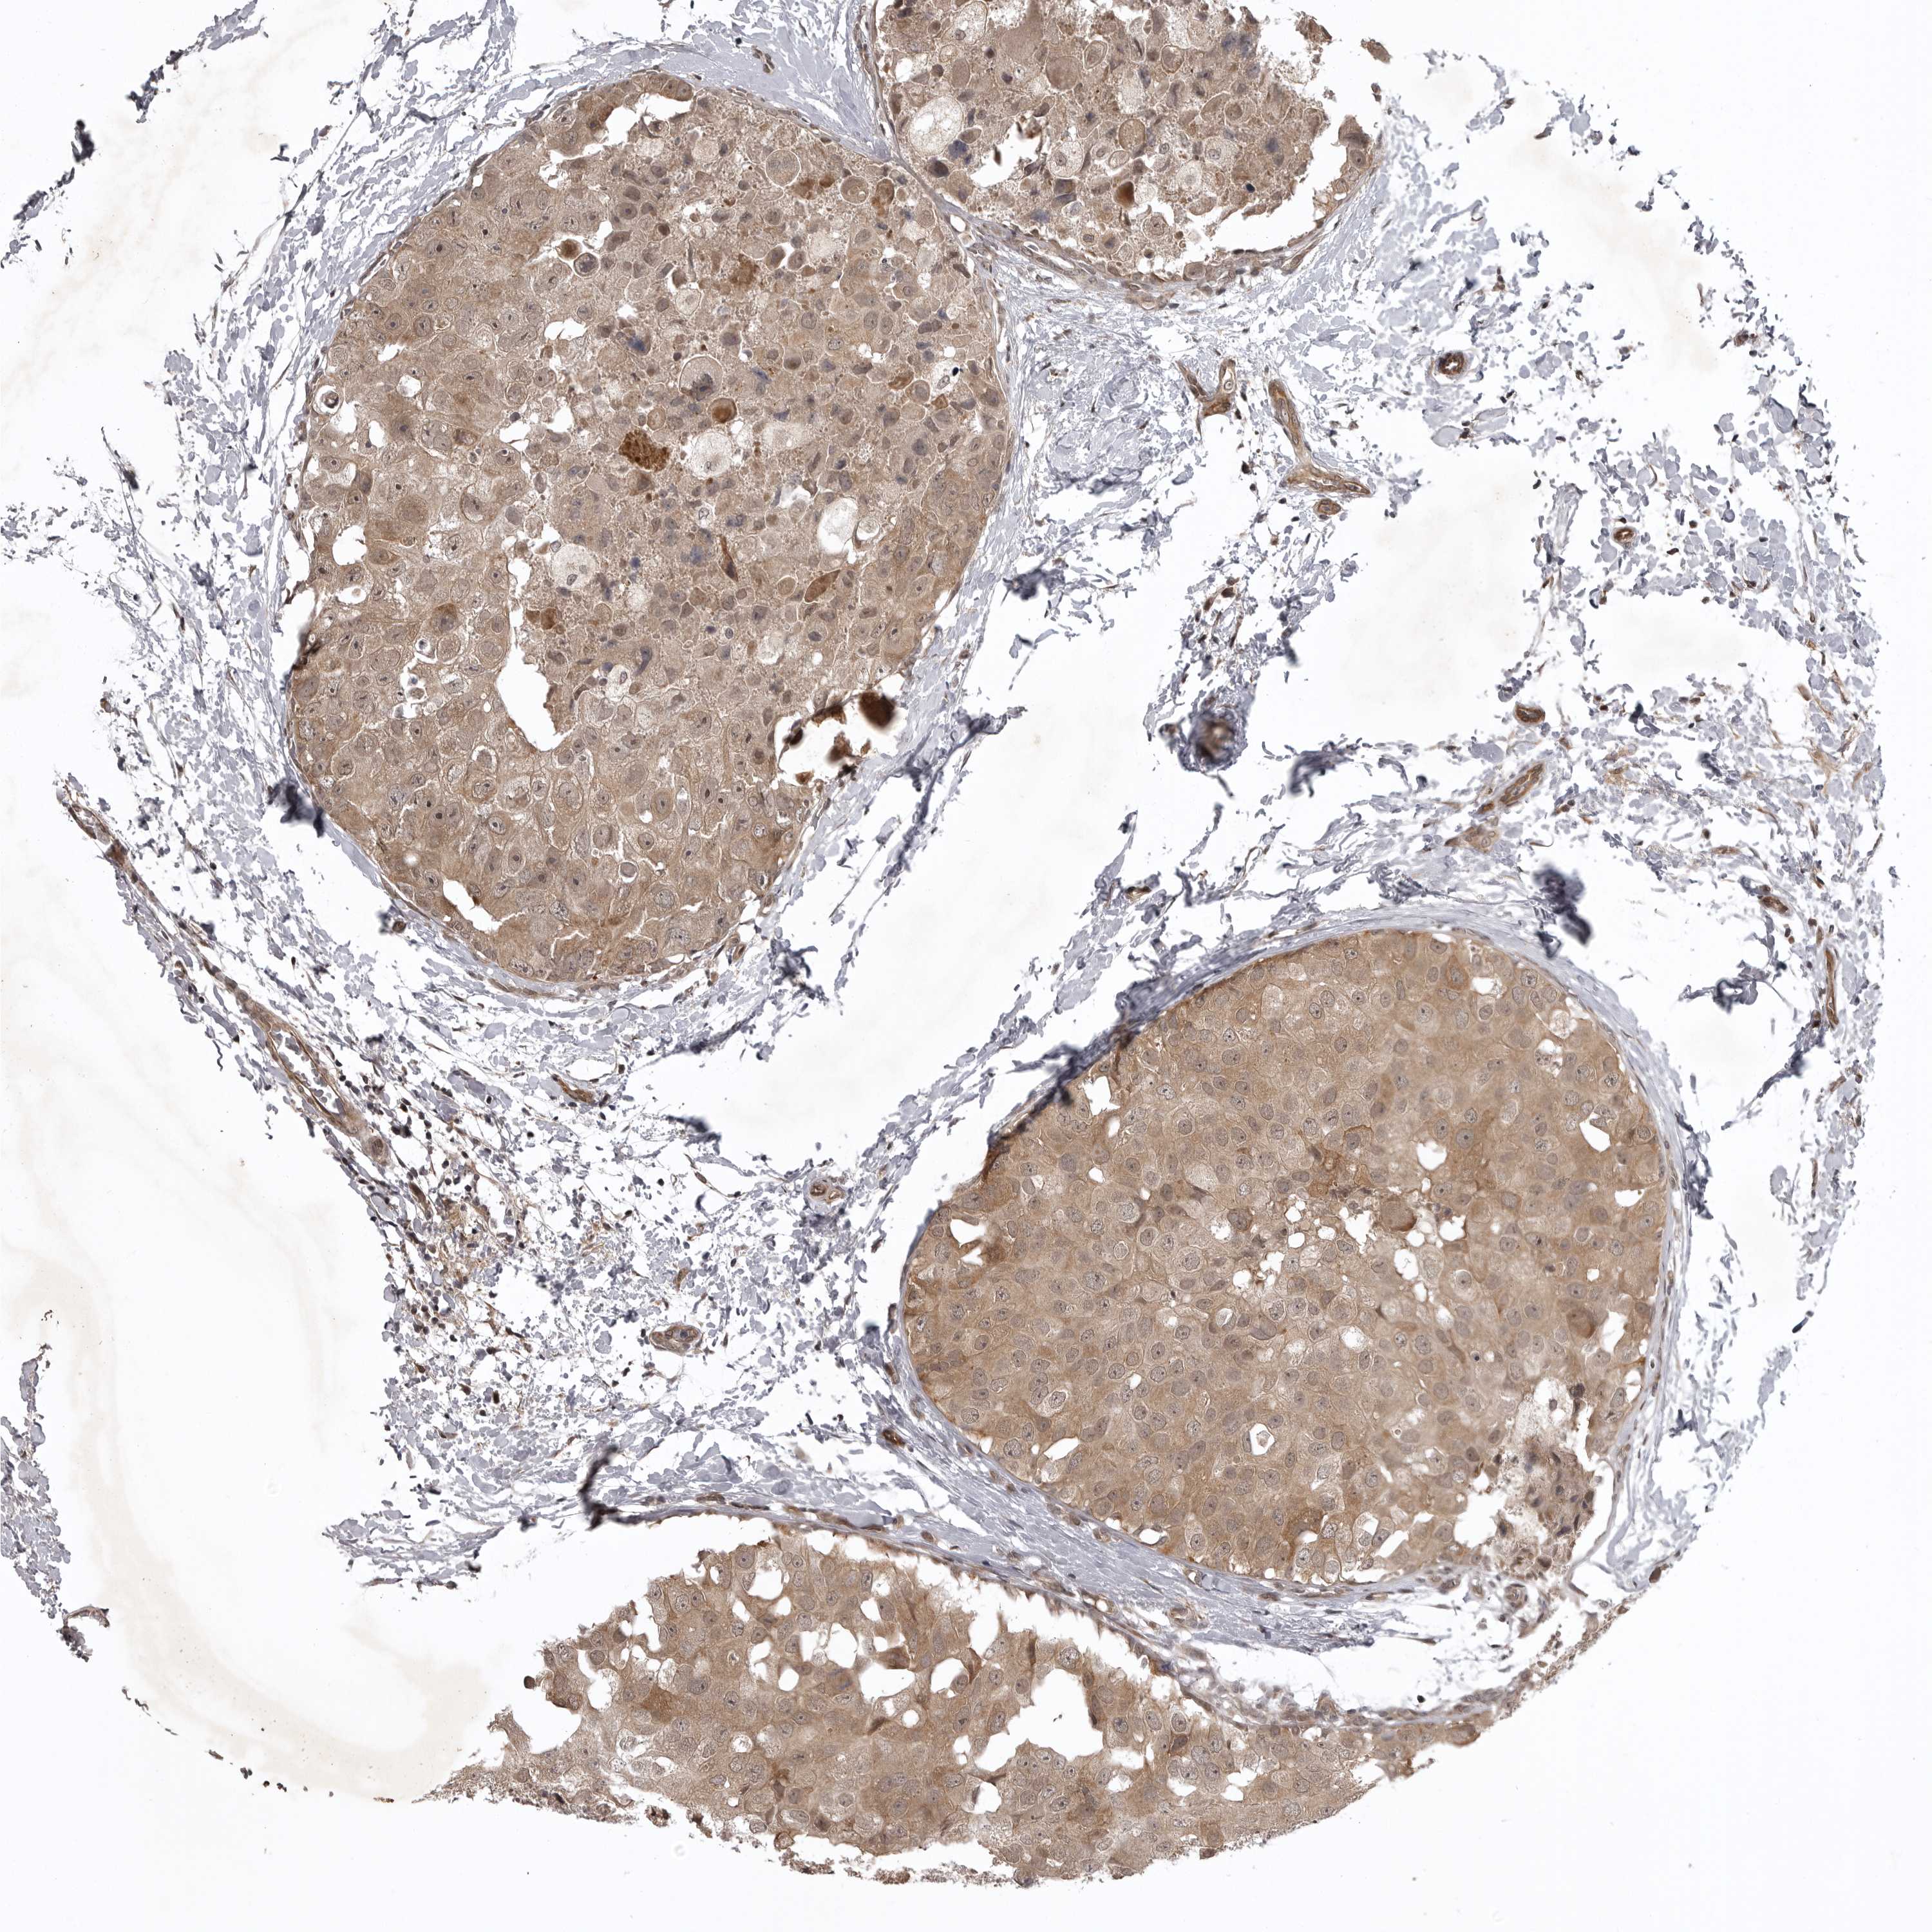

BRCA TCGA BRCA VALIDATION PROTEIN EXPRESSION

ANTIBODIES

AND

VALIDATION